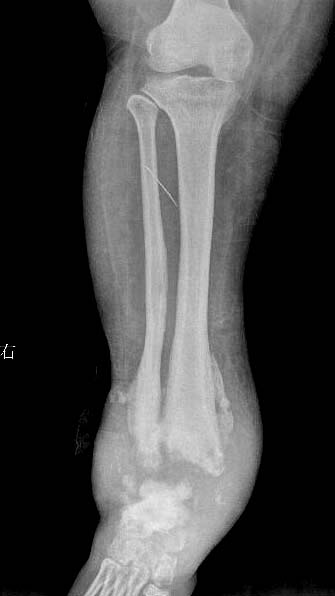

女.29岁.先天髋关节脱位.腰椎后部向外膨出.外院诊断骨肉瘤.我院诊断夏科氏关节病。

女.29岁.先天髋关节脱位.腰椎后部向外膨出.外院诊断骨肉瘤.我院诊断夏科氏关节病请大家讨论!

该患者有脊柱裂和右侧髋臼发育不良,踝关节改变符合神经性骨关节病,必要时结合临床排除结核.

支持:1、脊柱裂;

2、右侧髋臼发育不良伴半脱位;

3、双踝关节夏科氏关节病。

1,双踝夏科氏关节;

2,右侧扁平髋并右髋关节半脱位;

3,脊柱裂.

x1147手术病理双踝夏科氏关节病、右下肢骨髓炎瘘道形成感染截肢!

踝关节表现好像是夏科氏关节病

1、脊柱裂;伴脊髓脊膜膨出?建议mri检查,